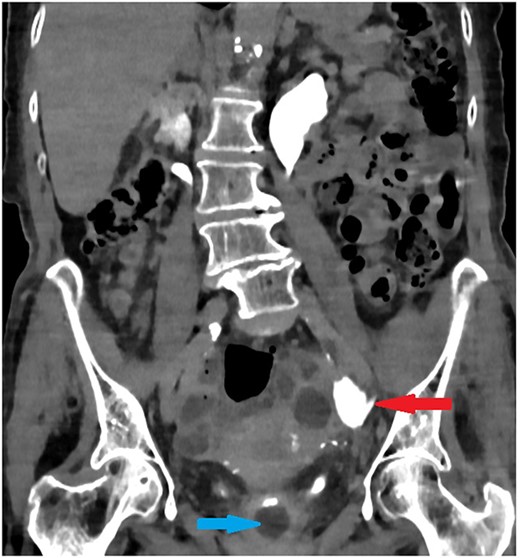

The old catheter was removed, and a replacement was inserted correctly into the bladder. The patient was managed conservatively with antibiotics. A further contrast CT was performed and showed mild extravasation of the contrast at the same level of the former catheter’s inflated balloon (Fig. 2). The patient improved clinically with conservative management, and her blood investigations remained stable. Follow-up contrast CT after 2 months was normal and showed no extravasation and no stricture (Fig. 3).

Coronal section of abdomen and pelvis contrast CT 2 weeks after the injury: Contrast flows normally without extravasation or stricture in the left ureter.